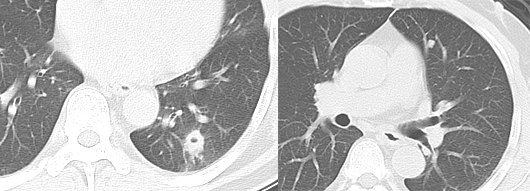

单发肺转移

无恶性肿瘤病史的患者单发肺转移的发生率很低(0.4 ~ 9.0%),有恶性肿瘤史的患者发生单发肺结节时 25 ~ 46% 为转移,且原发肿瘤多为腺癌或软组织肉瘤等。Cahan 总结 800 例肺孤立性肿物提出以下原则:原发肿瘤为鳞癌时肺内肿物多为原发,为腺癌时肺内原发和转移的概率各半,原发为软组织或骨肉瘤、黑色素瘤时肺内多为转移。CT 上单发转移瘤多数边缘光整,符合转移瘤特点,少数边缘可出现分叶、毛刺等,与原发肿瘤难以鉴别。

直肠癌术后 2 年,发现右肺结节 1 周。双肺仅见 1 枚结节,穿刺活检证实为直肠癌转移。